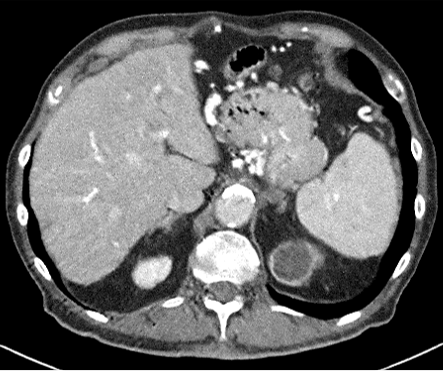

Figure 2: Comparison of generated Pseudo-LDCT images and their noise. (a) LDCT, (b) Random noise histogram, (c) Gaussian noise, (d) Ours. The right-bottom patch indicates the noise lying on each image. The noise quality of (b) and (c) shows that random noise cannot represent (a). In contrast, (d) shows almost similar to (a)

For evaluation, the 2016 AAPM Low-Dose CT Grand Challenge dataset[16] was used and split into 3 train and 7 test, respectively. It consists of abdominal LDCT and NDCT images obtained from 10 patients with image size 512×512512512512\times 512. The voxel space of CT images is 0.5mm×0.5mm0.5𝑚𝑚0.5𝑚𝑚0.5mm\times 0.5mm with 3mm3𝑚𝑚3mm slice thickness. To demonstrate that our method works with any existing learning method, we applied our method to N2C (Noise2Clean), N2N (Noise2Noise)[13], and N2V (Noise2Void)[11]. N2C is a supervised learning method that uses all available labeled paired data. N2N and N2V are self-supervised learning methods which use noisy pair images and masking schemes. Also, to demonstrate the effectiveness of our noise model, we compared LDCT denoising performance against existing noise generation techniques i.e. Random Noise histogram (Hist), Gaussian noise (Gaussian), and Single noise model++Noise histogram (Model+Hist). Hist samples noise from the difference map based on the histogram between LDCT and NDCT images, whereas gaussian samples the noise from a Gaussian distribution with zero mean and 0.02 standard deviation. Model+Hist is the combination of a single pre-trained LDCT noise model (using all subjects in the training dataset) and Hist. For evaluation, Peak Signal-to-Noise Ratio (PSNR) and Structural Similarity (SSIM) are reported.

Figure 3: Comparison of existing methods and Ours. (a) LDCT, (b) N2C, (c) N2N, (d) N2V, (e) NDCT, (f) N2C+Ours, (g) N2N+Ours, (h) N2V+Ours.

For parameter updates, it is crucial to generate high-quality Pseudo-LDCT images i.e. images similar to an actual LDCT image. If high-quality Pseudo-LDCT images are provided to the model for training, CT denoising performance can be improved. In contrast, using low-quality Pseudo-CT images may adversely affects the model learning, and consequently lead to decreased denoising performance. Table. 1 also shows the average PSNR and SSIM in different Pseudo-CT image generation settings. Here, both Hist and Gaussian reported lower performance compared to N2C. Based on our observations, this serves to show that random noise employed in natural images is not useful for CT denoising. In contrast, when our noise model was combined with Hist i.e. Model+Hist, performance gains over N2C were noted. This implies that our noise model can generate reasonable noise similar to the actual CT noise, and also improves performance. Furthermore, our ensemble noise models without parameter update show improved results over Model+Hist without the need for additional random noise.

In Figures 2 and 3, we show comparison results of Pseudo-LDCT images and their generated noise using various methods, as well as the predictions of our method for each. In Fig. 2, Pseudo-LDCT images and their noise with Hist and Gaussian highlight a huge discrepancy between the actual LDCT image and its noise. In the case of random noise that is shown to be independently distributed across the entire image, it is often useful for natural image denoising. Moreover, this types of noise does not accurately reflect the nature of CT images. Through the proposed method, we show it is possible to generate Pseudo-CT images that preserve overall CT image characteristics with high quality (Fig. 3).